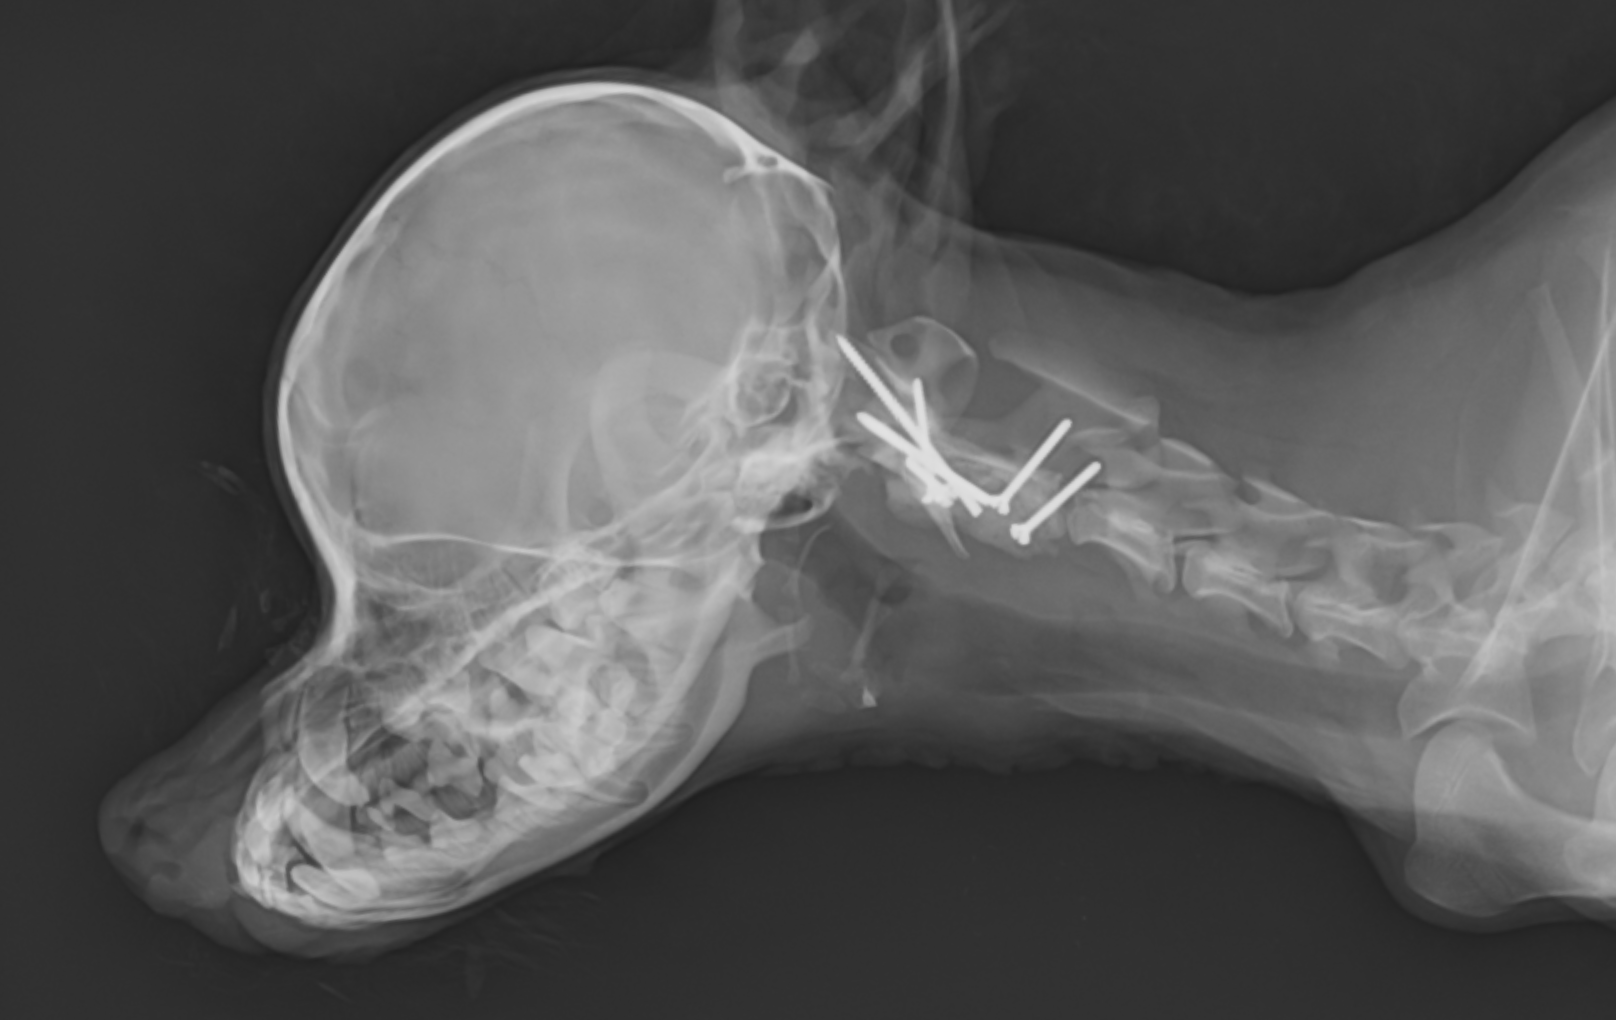

終了後のレントゲンです。

術後レントゲンです。8本のピンが刺入されているのが分かります。術後からとても経過はよく、1週間後には歩行可能となり、3ヶ月経過現在元気に歩き回っています。